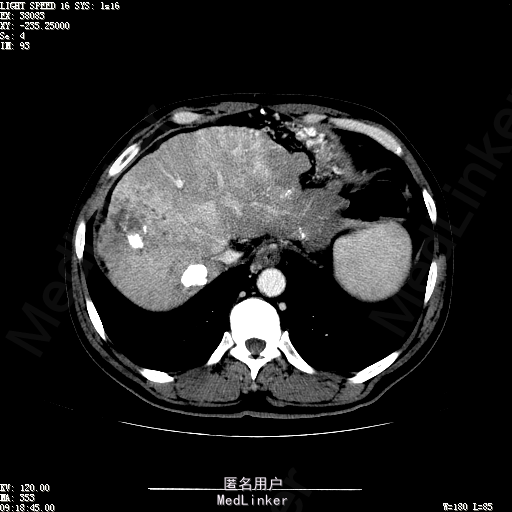

查体:生命体征平稳,神志清晰,发育正常,营养中等,体位自如,表情安静,无面容,配合检查合作。皮肤粘膜颜色正常,腹型平坦,无腹壁静脉曲张,未见胃肠型及蠕动波,无瘢痕,脐部正常。触诊:无压痛,无反跳痛,无腹肌紧张,无腹部包块。肝未触及,Murphy征阴性,脾未触及,肾未触及,无移动性浊音。 化验回报:血细胞分析(五分类):*白细胞计数 4.6 10^9/L、红细胞计数 4.27 10^12/L、血小板计数 100.0 10^9/L、血红蛋白 145 g/L、中性粒细胞百分比 68.6 %,*葡萄糖测定:葡萄糖 5.99 mmol/L,血清离子测定:*钾 4.46 mmol/L、钠 143.5 mmol/L,肾功能检测:*尿素 6.86 mmol/L、肌酐 84.2 umol/L,凝血五项:凝血酶原时间 10.7 秒、凝血酶原百分活动度 93.3 %,乙肝六项:乙型肝炎病毒表面抗原 阳性(+) 、乙型肝炎病毒e抗体 阳性(+) 、乙型肝炎病毒核心抗体 阳性(+) ,甲胎蛋白测定:甲胎蛋白 7146.00 ng/mL,ALT23U/L,AST42U/L CT检查如下图

诊断:乙肝肝硬化 静止性 代偿期 原发性肝癌 2型糖尿病 高血压病 下肢动脉闭塞征 诊断依据:1.有明确乙肝肝硬化病史 2.肝区隐痛,于外院发现肝占位,我院诊断肝癌,已行TACE治疗 3.查体:有肝掌 4.既往影像学提示肝内占位 处置:血管介入治疗:患者平卧位,以左侧肘窝为中心常规消毒、铺巾、利多卡因局麻。超声引导下,于肘横纹上方1厘米处确定皮肤穿刺点,改良Seldinger法逆行穿刺左侧肱动脉成功,置入5F血管鞘。沿导丝送入Cobra C2导管,送入降主动脉,将管头送入腹腔干,进一步送至肝固有动脉。造影见肝内广泛弥漫肿瘤染色,以右叶为主。以微导管超选肝右动脉,造影明确为肿瘤供血动脉,注入碘化油5毫升。退出微导管,经C2管注入奥沙利铂100毫克。退出C2管。拔出血管鞘,局部压迫10分钟。加压包扎。患者送返病房。